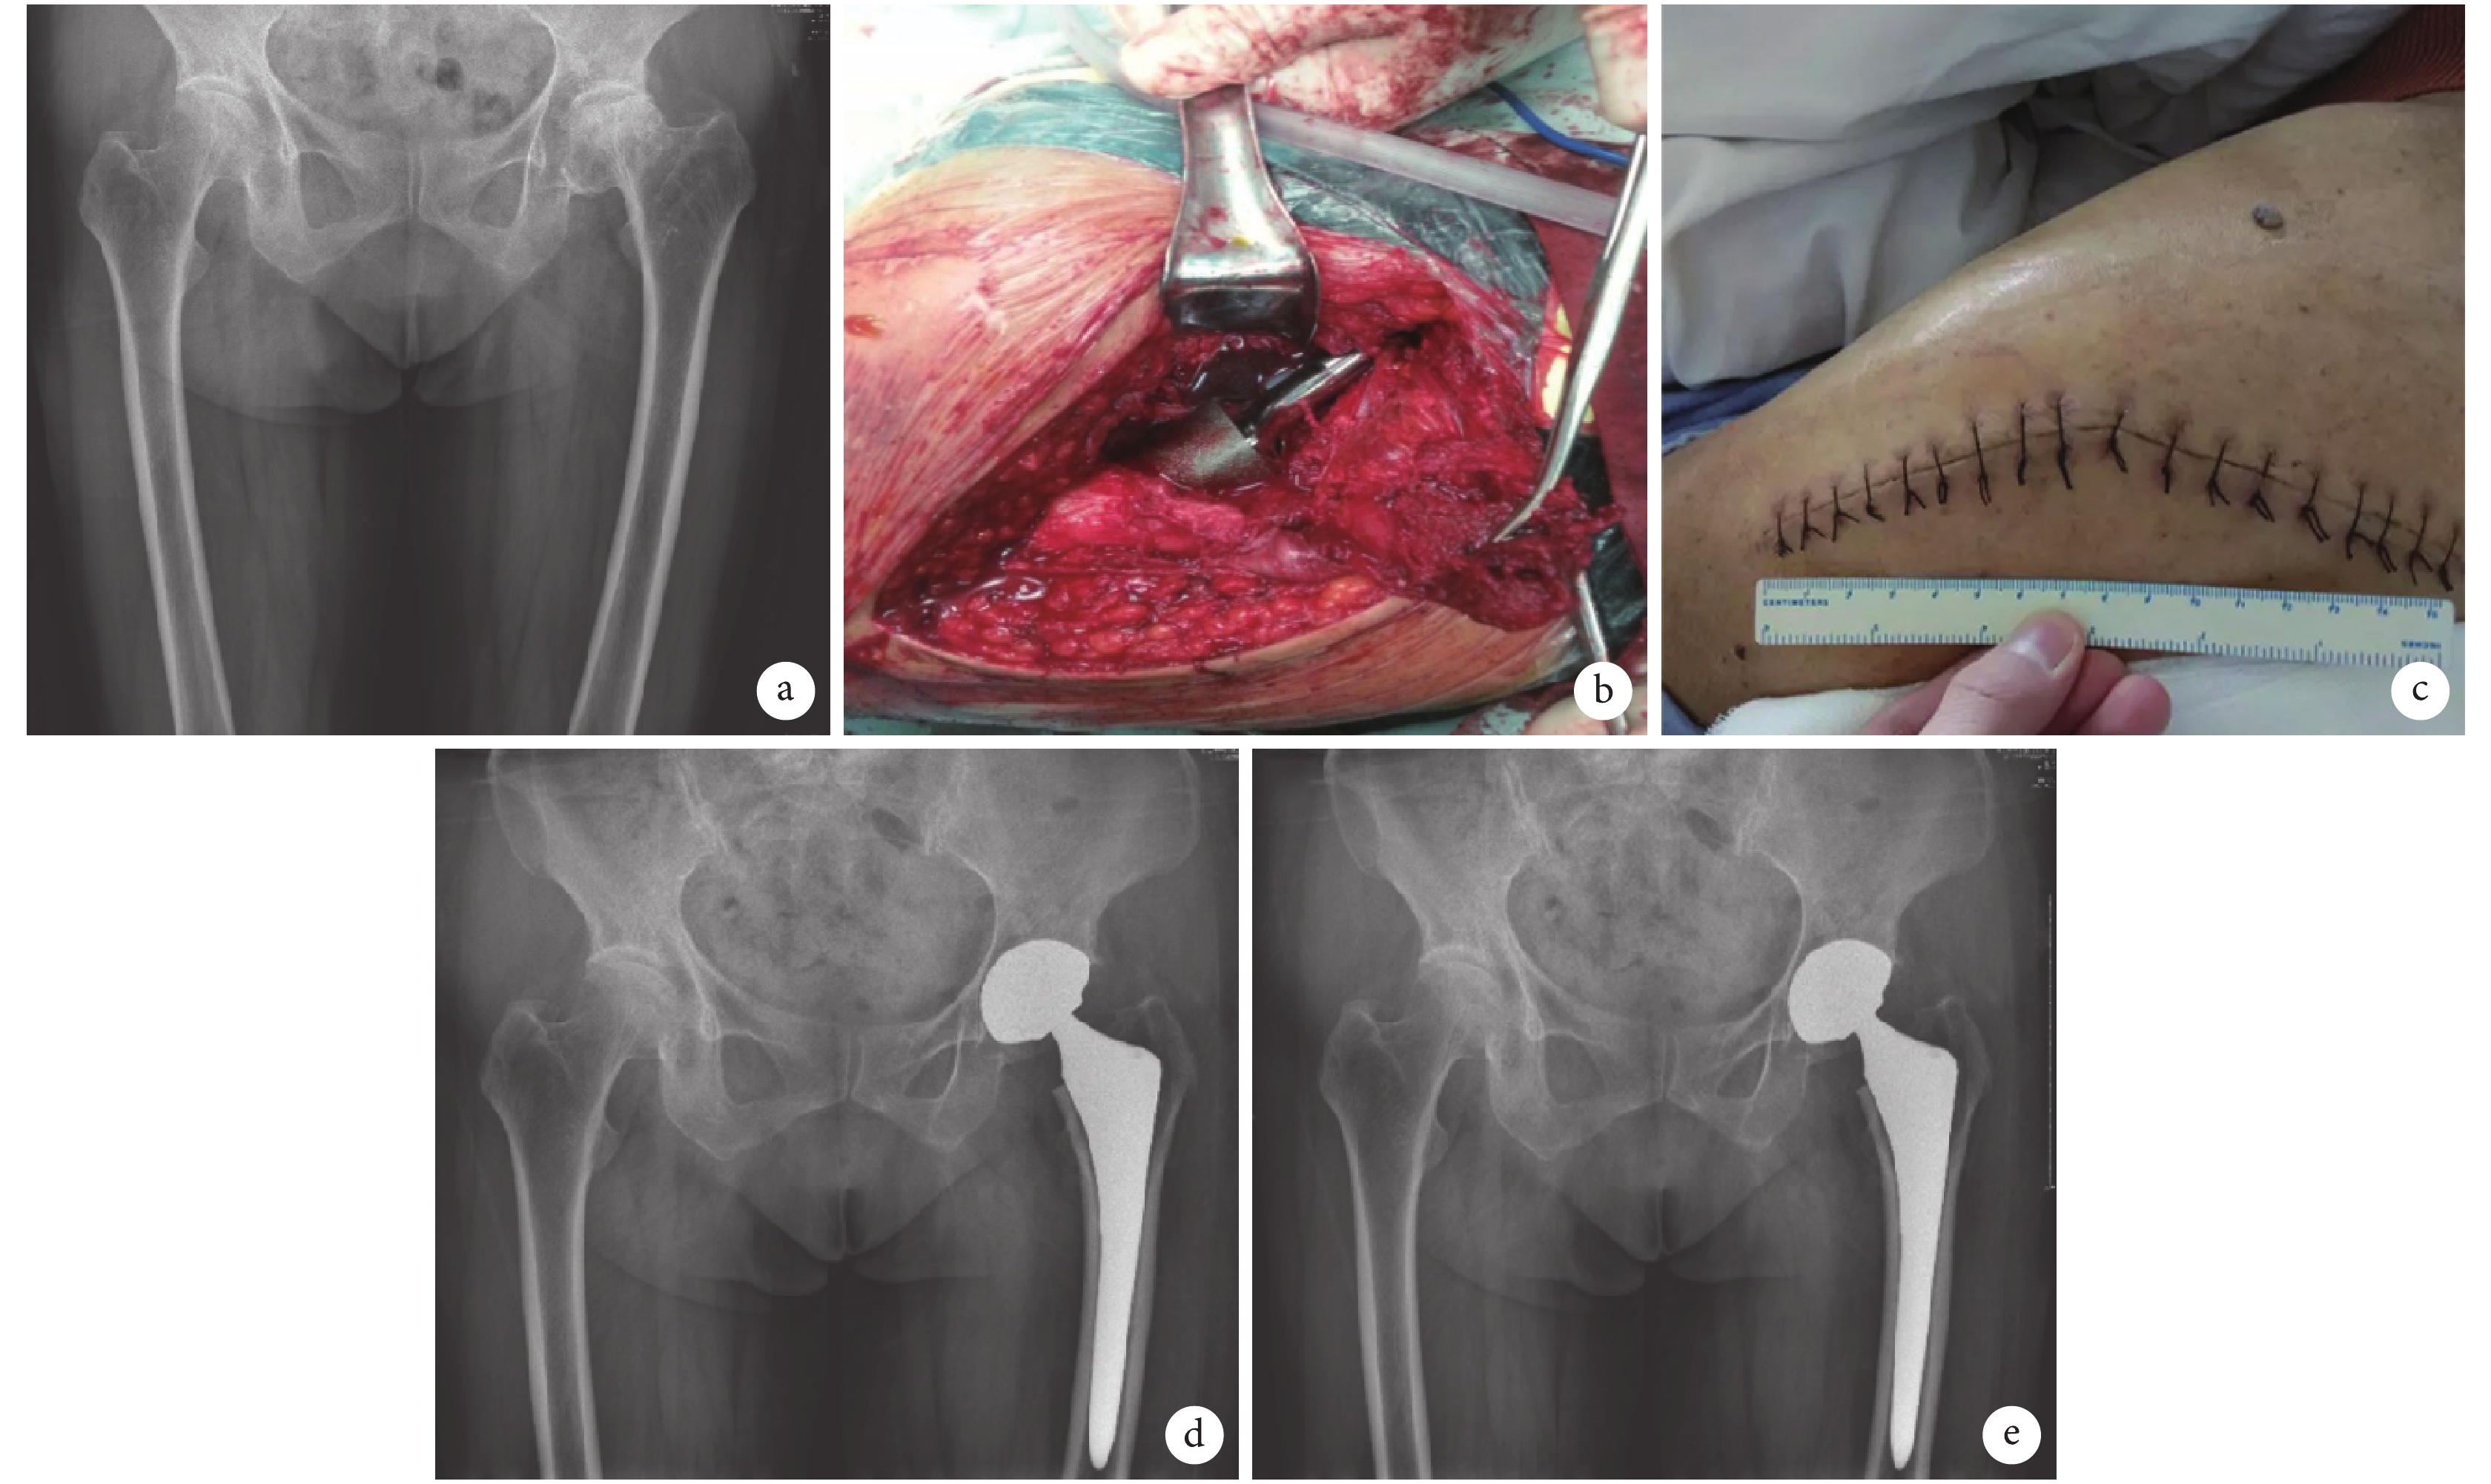

兩組患者術后均獲隨訪,隨訪時間 6~18 個月,平均 10.3 個月。SuperPATH 組手術時間、術中失血量、切口長度、術后引流量及下地時間均優于 PSA 組,比較差異有統計學意義(P<0.05)。見表 2。SuperPATH 組術后 2 周及 1 個月時 Harris 評分顯著優于 PSA 組,比較差異有統計學意義(P<0.05);術后 3、6 個月時兩組比較差異無統計學意義(P>0.05),見表 1。末次隨訪時,SuperPATH 組 SF-36 量表評分中的活力、軀體疼痛、社會功能以及總體健康評分均高于 PSA 組,比較差異有統計學意義(P<0.05)。見表 3。術后 X 線片復查示假體位置良好。見圖 1、2。

a. 術前 X 線片;b. 術中經臀中肌、臀小肌與梨狀肌間隙顯露髖關節囊;c. 術后即刻切口外觀;d. 術后 1 d X 線片;e. 術后 1 個月 X 線片

Figure1. A 74-year-old male patient with the left femoral neck fracture (Garden type Ⅳ) in SuperPATH groupa. Preoperative X-ray film; b. The hip capsule was exposed between the gluteus mediue, gluteus minimus, and piriformis during operation; c. Incision appearance at immediate after operation; d. X-ray film at 1 day after operation; e. X-ray film at 1 month after operation